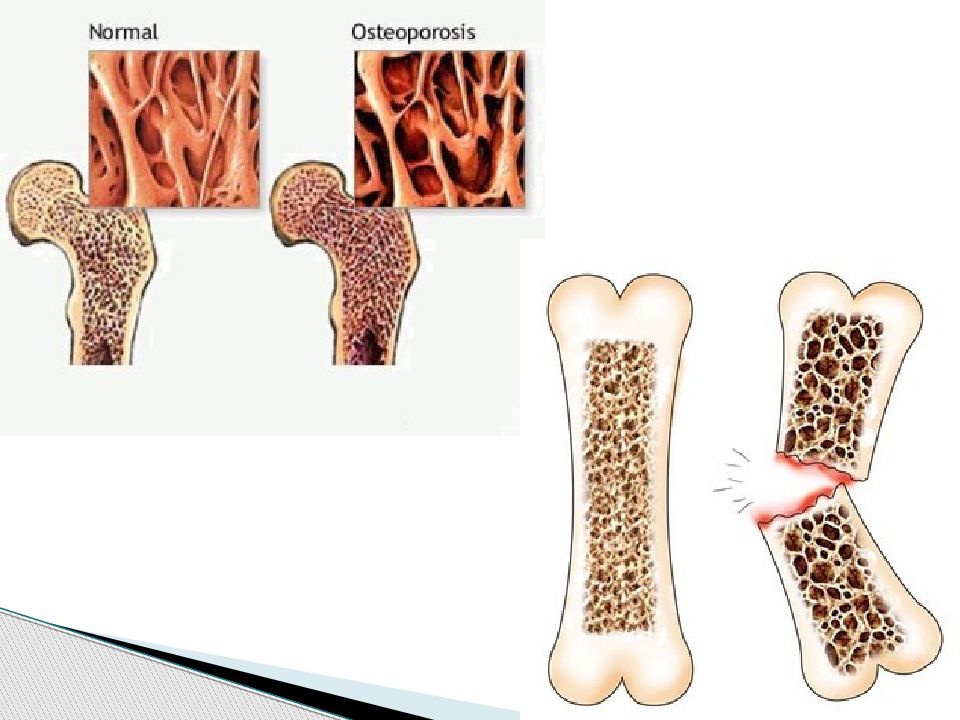

Иллюстрации и схемы по остеопорозу и паращитовидной железе

Раздел: Картинки жизни